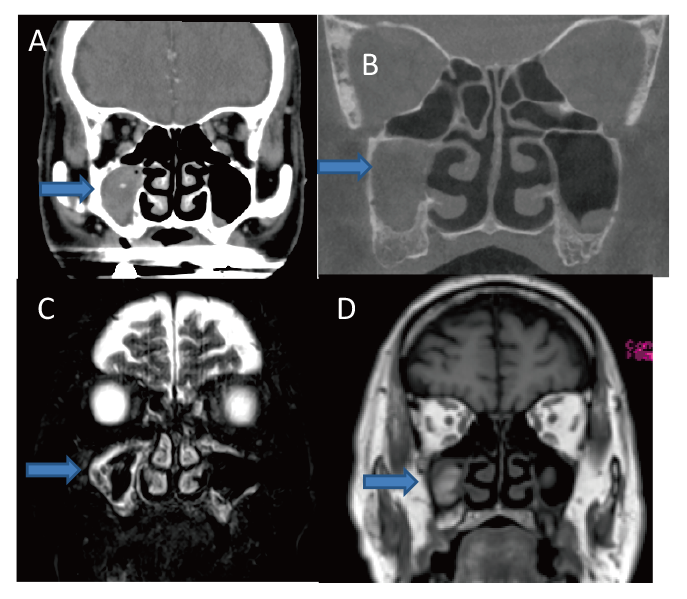

71-year-old male. (A) MDCT showing intrasinus calcification in the right maxillary sinus. (B) CBCT showing no intrasinus calcification. (C) MRI showing hypointense signal mass on T2-weighted image. (D) MRI showing isointense signal mass on T1-weighted image.

Although it is not the direct comparison of CBCT and MDCT using the same patients, density of intrasinus calcification in CBCT group was higher than that in MDCT group (Fig. 1). Limited contrast resolution could be the reason of the result, because if the density of calcification is low in CBCT, it could be difficult to distinguish calcification from surrounding soft tissue. In other words, there is a possibility that CBCT could not detect faint calcification. Indeed, in three patients of CBCT group (23.1%), CBCT could not detect calcification but MDCT could (Table 2). In these cases, mean HU of calcification detected by MDCT was 118±45.

Zinreich et al. reported that remarkably hypointense signals on T2-weighted images were characteristic MRI findings of the fungal sinusitis5). In our study, nine out of the 13 patients in the CBCT group and 28 out of 38 patients in the MDCT group underwent MRI, and all the patients showed hypointense signals or signal void areas on T2-weighted images. Although sensitivity of these MRI findings was 100% in our series, the sensitivity of MRI in the previous literature varies from 50%10) to 100%5,11). As Nicolai and Nomura mentioned, these MRI findings is not specific to fungus ball. The presence of air, acute hemorrhage or eosinophilic mucin might decrease the signal intensity in T2-weighted images10,11). In our series, these factors decreasing the signal intensity in T2-wheighted images were excluded from preoperative CT images, intraoperative findings and pathological diagnoses. In our facility, CBCT is conducted as the first step of image evaluation for sinusitis due to the low radiation dose and excellent spatial resolution of bone lesions. MRI is performed as the second step when intrasinus calcification is absent or detailed soft tissue evaluation is necessary (Fig. 2). If intrasinus calcification is not found on CBCT findings, MDCT is not the second choice because radiation exposure will be higher if both CBCT and MDCT are performed. At present, MDCT as the second step is justified only when MRI is contraindicated or malignancy is highly suspected. In these settings, MDCT should be performed with contrast medium.